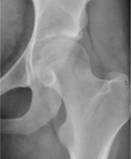

Note: (1) the progressive roughening of the round ball and its socket,

(2) the decreasing clear space (cartilage and fluid) between them,

(3) and the extra rough bone (white material) around the joint.

https://upload.wikimedia.org/wikipedia/commons/5/51/X-ray_of_a_normal_hip_joint.jpg

https://commons.wikimedia.org/wiki/File:X-ray_of_a_normal_hip_joint.jpg

Description English: For context, see: en:Hip pain